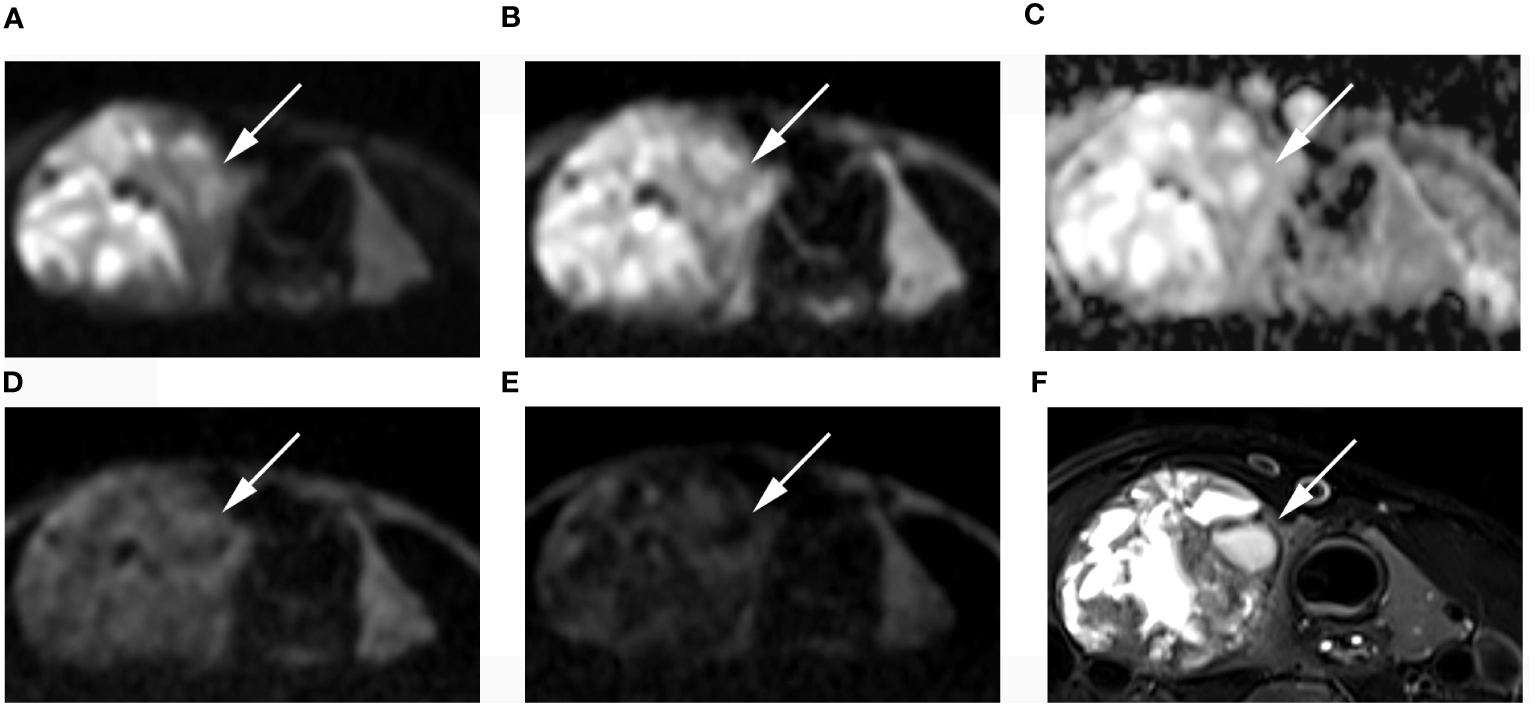

Figure 5 Images of a 49-year-old female with right lobe follicular adenoma (arrow): DWI image with a b-value of 500 s/mm2 (A), 1000 s/mm2 (B), 1500 s/mm2 (D), 2000 s/mm2 (E); (C) ADC image with a b-value of 1500 s/mm2; (F) T2-weighted image. The SNR of thyroid decreased as the b value increased. In the DWI image with a b-value of 1500 s/mm2, the SI of the nodule was significantly low relative to the other images.